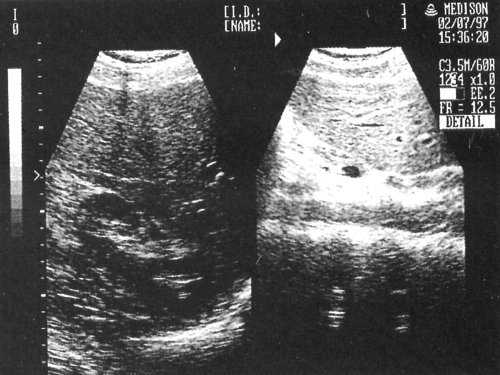

При УЗИ и дуплексном сканировании сосудов брюшной полости печень не увеличена в размерах, переднезадний размер правой доли - 136 мм, левой доли - 66 мм, контуры четкие, структура паренхимы однородная, диффузно уплотнена. Желчный пузырь не увеличен, визуализируется с перегибом, стенки утолщены, содержимое однородное. Внутри- и внепеченочные желчные протоки не расширены. Гепатикохоледох определяется, диаметром 3,6 мм, просвет его свободный. Поджелудочная железа не увеличена в размерах, головка - 30 мм, тело - 11 мм, хвост - 18 мм. Контуры железы в проекции тело - хвост ровные, четкие, структура паренхимы однородная, диффузно уплотнена. Главный панкреатический проток не визуализируется. В проекции гепатодуоденальной связки определяется кистозное образование овальной формы, с четкими ровными контурами, размером 47,0x33,4 мм, по структуре анэхогенное, неоднородное с наличием эхоплотных, неравномерно выраженных перегородок в эхоплотной капсуле толщиной до 2,8 мм (рис. 2, а). При дуплексном сканировании данных о наличии кровотока в капсуле и перегородках образования не получено. По заднему контуру образования прослеживается ход общей печеночной артерии (рис. 2, б) без гемодинамически значимых изменений скорости кровотока.

Рис. 2. УЗ-картина кистозного образования (отшнуровавшейся дупликационной кисты двенадцатиперстной кишки) в проекции гепатодуоденальной связки.